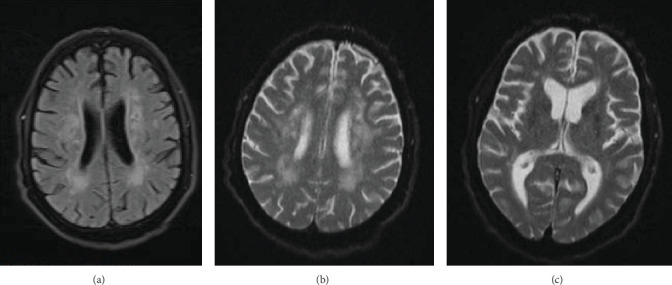

Background: Fahr's syndrome is a rare neurodegenerative condition characterized by bilateral progressive calcification of the basal ganglia and other brain structures. Due to overlapping symptoms, it can be misdiagnosed as other neurological disorders. Case presentation: A 68-year-old man was presented to the emergency department with an exacerbating decline in the level of consciousness and dysarthria over a 20-day period. On admission, the laboratory examinations revealed a low level of calcium and parathyroid hormone. Brain imaging findings showed bilateral calcifications in the basal ganglia, pulvinar region of the thalami, and dentate nuclei. In addition, a prolonged QTc interval on his electrocardiogram (ECG) indicated hypocalcemia. After receiving calcium gluconate 10%, the calcium level and QTc interval stabilized, and the patient's level of consciousness gradually improved. Conclusion: Fahr's syndrome due to hypoparathyroidism should be suspected in any patient with neurological symptoms and hypocalcemia. Hence, early identification and management of hypoparathyroidism can prevent progression of calcification and improve patients' quality of life and prognosis.